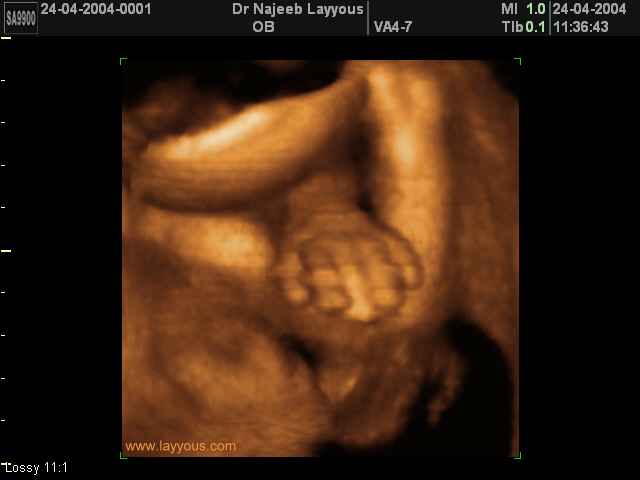

3D Ultrasound Scan Photos of Fetal Limbs | Dr N Layyous

3D Fetal Limbs Ultrasound Scan Photos